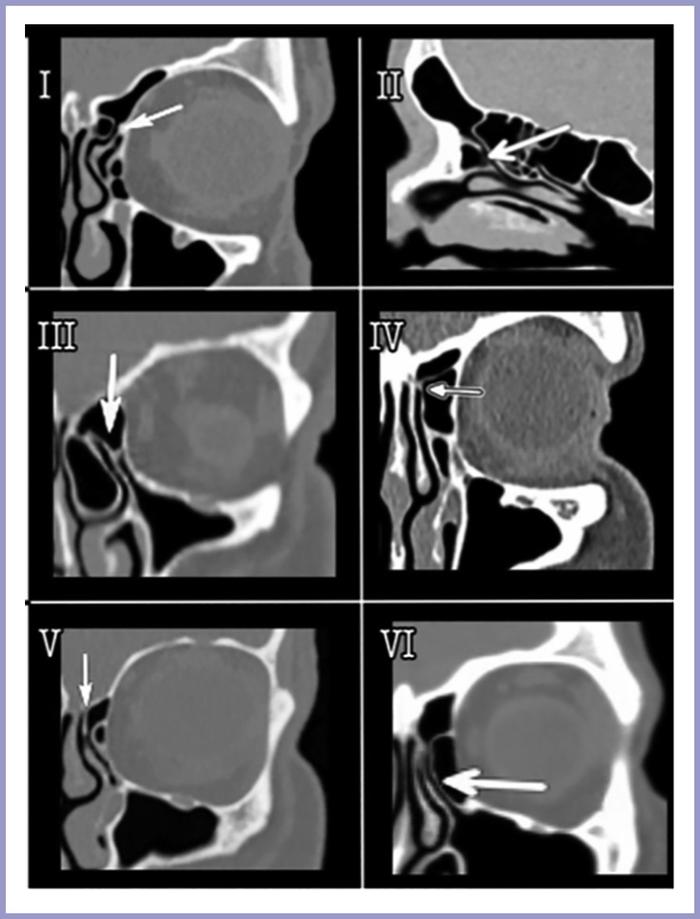

Рисунок 2. Различные типы SAUP. Результаты компьютерной томографии.

Обнаружено, что латеральные формы SAUP (типы I, II и III) чаще встречаются при наличии ламеллярных клеток [32]. Примечательно, что при латеральной локализации SAUP лобный карман открывается непосредственно в средний носовой ход, к медиальной стороне от крючковидного отростка. Таким образом, при таких условиях наблюдается более высокий риск фронтита [34, 35].